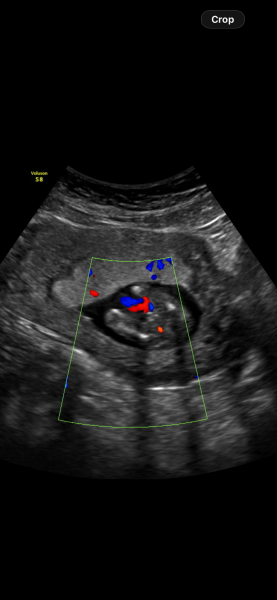

16-week scan: does this look like a boy to others?

Definitely a boy? Doesn’t look the same as my other 2 sons (16 weeks). I hope it is as I’ve gone and bought all boy things and so excited for him to arrive. However I showed someone these and they’re not convinced.